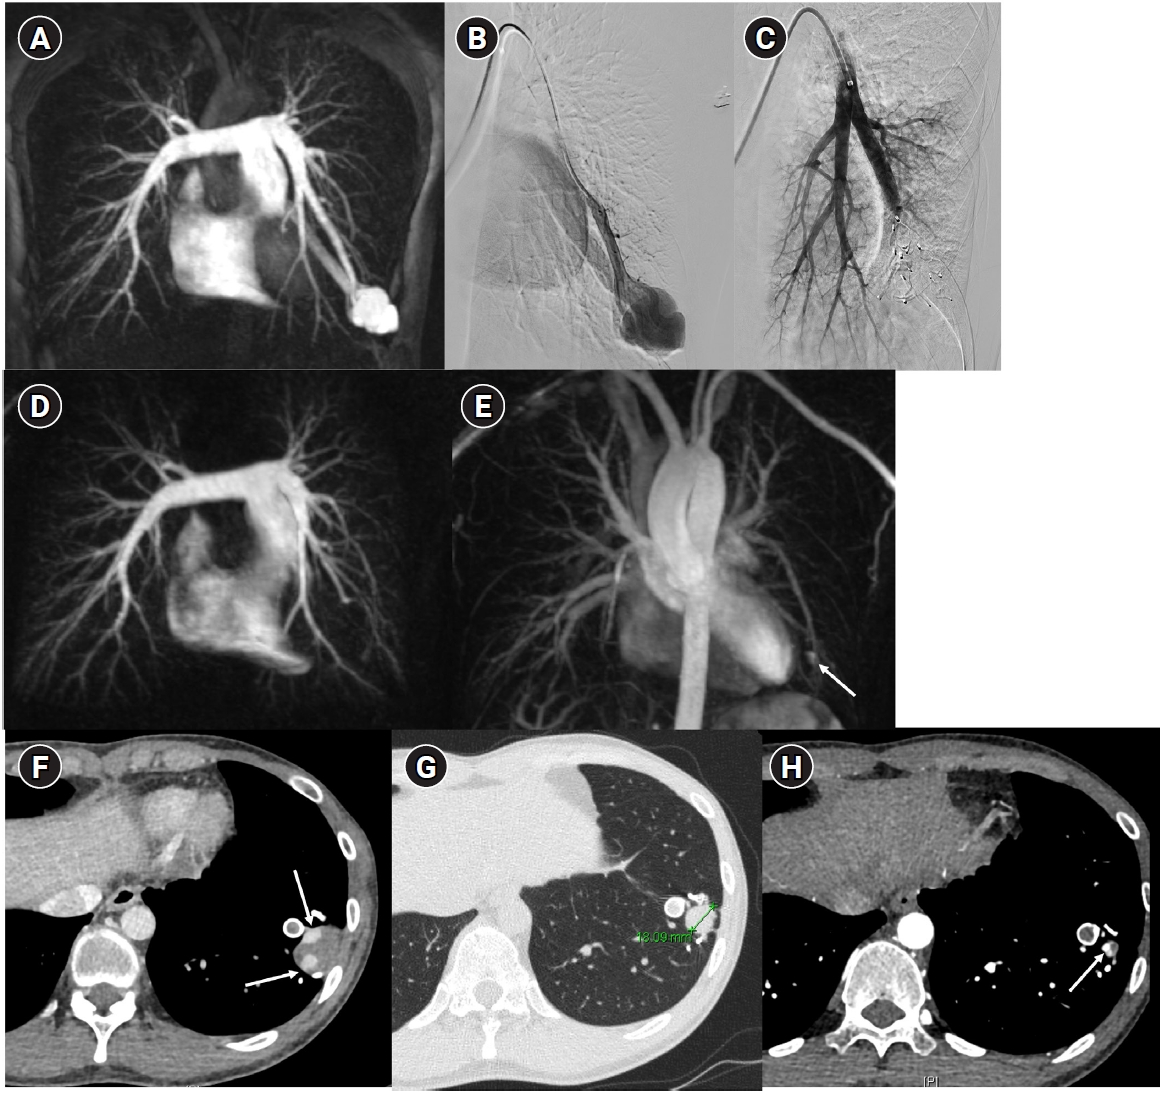

Fig. 4.

The images show a 38-year-old female patient undergoing pulmonary arteriovenous malformation embolization using an Amplatzer vascular plug. (A) A simple pulmonary arteriovenous malformation is observed in the right pulmonary angiography, and the feeding artery diameter is measured at 3.7 mm. (B) An 8-Fr, 80-cm guiding catheter and a 5-Fr Berenstein angled catheter were used to advance to the distal end of the feeding artery. (C) A 7-mm Amplatzer vascular plug type IV (arrow) was deployed at the distal portion of the feeding artery with a 100% oversizing. (D, E) The large venous sac (arrow) that was visible on the pre-procedure non-enhanced chest computed tomography (CT) (D) had only a trace remaining (arrow) on the CT performed 6 months later (E).

Historically, detachable balloons were used as an embolization material; however, they are no longer utilized in current practice [18]. In the context of PAVM embolization, the use of coils, vascular plugs, or a combination of both is now standard practice [19-21]. Since the development of detachable coils, they have offered advantages over pushable coils, particularly in terms of repositioning during the procedure. They can even be fully retrieved and redeployed if necessary, enhancing procedural safety and control. It is crucial to prioritize minimizing the recanalization rate while ensuring the overall safety of the procedure when selecting the appropriate embolic materials and techniques. Feeding artery coil embolization was historically regarded as the standard approach, whereas venous sac embolization was discouraged because of the perceived risk of rupture [22]. However, with the introduction of newer venous sac embolization techniques, recent findings now indicate that tightly packing the venous sac with coils can achieve a higher success rate than the traditional feeding artery approach (Fig. 2) [22-25]. Additionally, vascular plugs, including micro-vascular plugs (Medtronic, Minneapolis, MN, USA) and Amplatzer vascular plugs (Abbott Vascular, Saint Paul, MN, USA) have also demonstrated a higher success rate compared to feeding artery coil embolization (Fig. 4) [26-28]. In the case of vascular plugs, the risk of device migration is relatively low. Moreover, an additional advantage is that the device can be repositioned if the sizing is not ideal or if it is not deployed in the exact desired location. This flexibility enhances the precision of the procedure (Fig. 5). In a recent European guideline, there is also a recommendation to consider vascular plug embolization as a first-line option whenever possible, rather than coil embolization [11]. Additionally, a recent meta-analysis recommended vascular plugs or venous sac coil embolization, noting that vascular plugs had a recanalization rate of 13.6% compared to 32.7% for coil-only embolization. Similarly, venous sac embolization showed a 3.8% recanalization rate, while feeding artery embolization had a rate of 24.3%. Additionally, a recent meta-analysis has recommended the use of vascular plug or venous sac coil embolization, as these techniques have demonstrated a lower persistence rate compared to other methods [21]. This shift is largely in response to the relatively high recanalization rate associated with feeding coil embolization. In the case of embolization using vascular plugs, the plug should be deployed at the most distal segment of the feeding artery just before the venous sac in order to preserve the normal pulmonary artery. Since the pulmonary artery contains less elastin and has a thinner wall compared to systemic arteries, it is more distensible [29]. Therefore, in the author's experience, oversizing by about 50% to 100% has been effective in reducing the recanalization rate. When performing venous sac coil embolization, it is important to use coils large enough to create a stable framing coil larger than the draining vein diameter, thereby preventing coil migration. After establishing this frame, the venous sac and the proximal feeding artery should be carefully packed to achieve complete occlusion.

Fig. 4. The images show a 38-year-old female patient undergoing pulmonary arteriovenous malformation embolization using an Amplatzer vascular plug. (A) A simple pulmonary arteriovenous malformation is observed in the right pulmonary angiography, and the feeding artery diameter is measured at 3.7 mm. (B) An 8-Fr, 80-cm guiding catheter and a 5-Fr Berenstein angled catheter were used to advance to the distal end of the feeding artery. (C) A 7-mm Amplatzer vascular plug type IV (arrow) was deployed at the distal portion of the feeding artery with a 100% oversizing. (D, E) The large venous sac (arrow) that was visible on the pre-procedure non-enhanced chest computed tomography (CT) (D) had only a trace remaining (arrow) on the CT performed 6 months later (E).